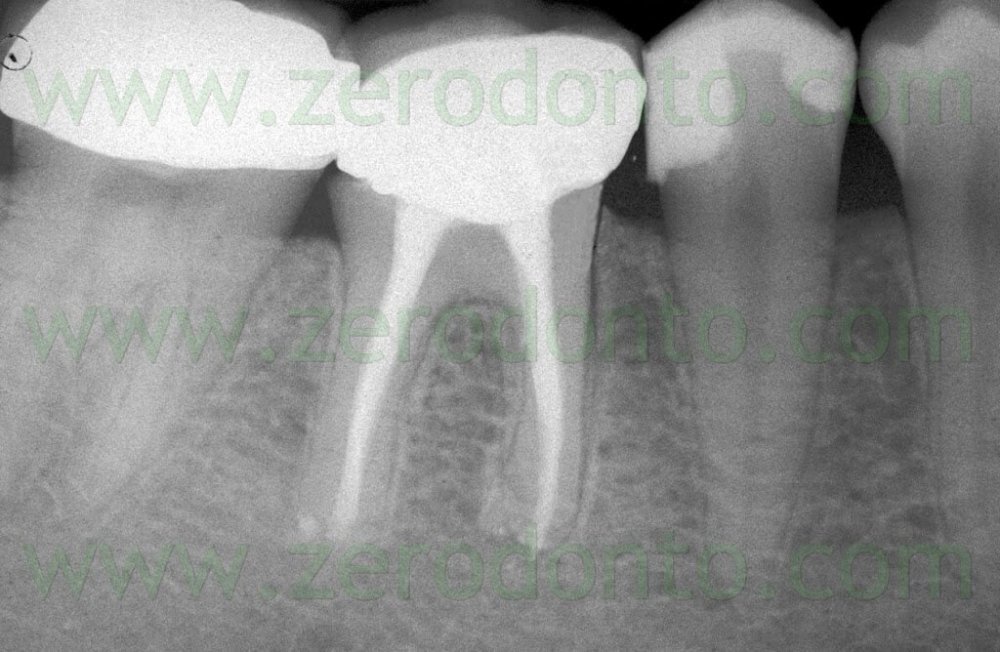

Bu zaman bəzi hallarda kanal müalicəsinin yenidən icrası (endodontik reviziya) mümkün olsa da, bir çox hallarda bu və ya digər səbəbdən həyata keçirilməsi mümkün olmur. Bu zaman əsas tətbiq edilən müalicə metodu dişi çəkməmək şərti ilə, iltihab ocağının uzaqlaşdırılmasını təmin edən – diş kökünün rezeksiyası metodudur. Bu əməliyyat vasitəsilə iltihab ocağı diş kökü ilə birlikdə kənarlaşdırılır və kök kanalları xüsusi metodla yenidən işlənir və doldurulur. Əməliyyat əsasən yerli ağrısızlaşdırma altında, xüsusi böyüdücü vasitənin tətbiqi ilə həyata keçirilir.

Uğurla tətbiq edildiyi halda uzun illər ərzində uğur vəd edən bir müalicə metodudur. Bu əməliyyat ağıl dişləri və bəzi hallarda 7-ci dişlər (ikinci böyük azı dişləri) istisna olmaqla digər bütün dişlərdə uğurla həyata keçirilə bilir. Müalicə metodunun uzunmüddətli uğurlu olmasında əməliyyatönü müayinənin ciddi şəkildə aparılması və dişlərin doğru seleksiyası xüsusi əhəmiyyət kəsb edir.